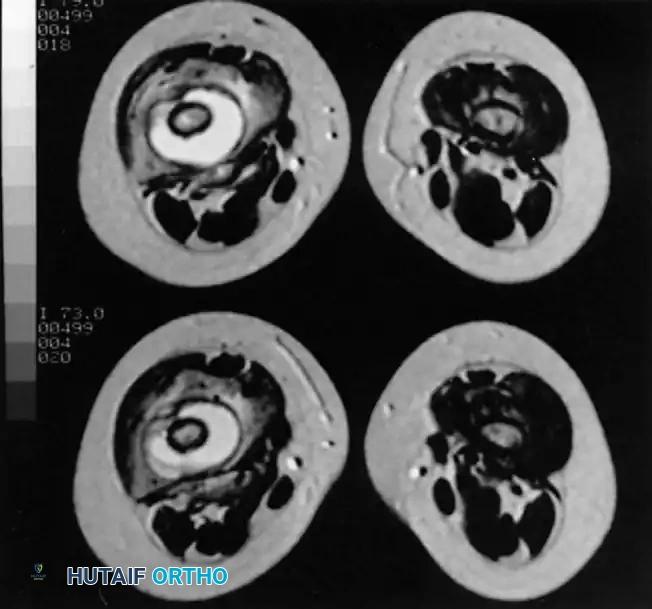

Image

Axial MRI slices demonstrating extensive marrow edema, cortical disruption, and surrounding soft-tissue abscess formation typical of advanced musculoskeletal infection.